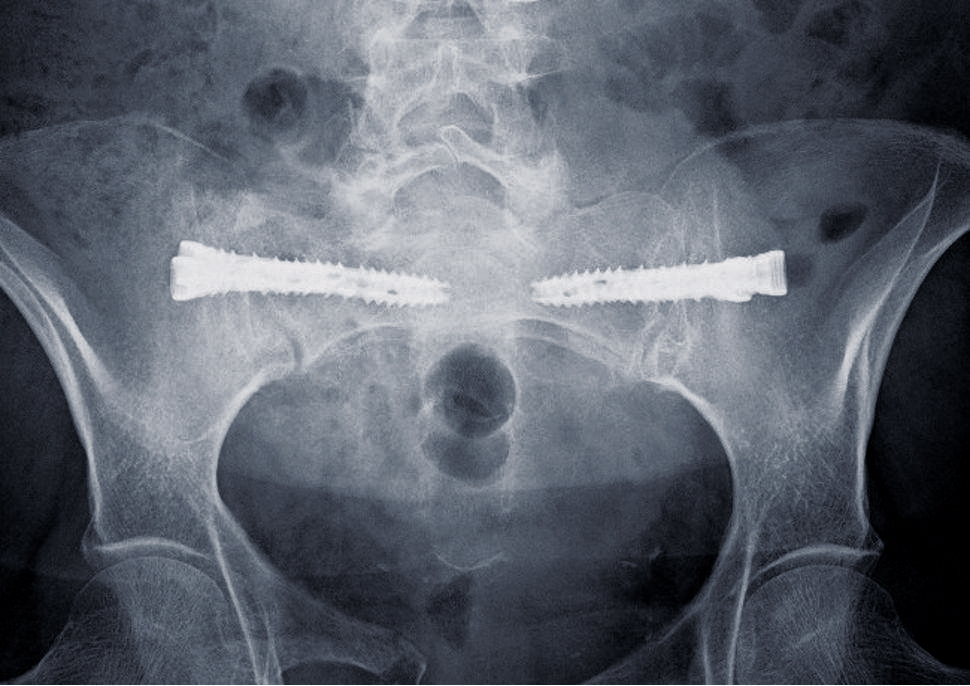

iFuse Torq™ – Röntgenaufnahme Fragilitätsfrakturen

iFuse Torq™ Fragilitätsfrakturen

Was ist der Vorteil der Verwendung von iFuse TORQ™-Implantaten bei Fragilitätsfrakturen des Beckens?

Cem König: Bei Patienten mit Fragilitätsfrakturen im Sakrum zeigten iFuse TORQ™-Implantate im Vergleich zur nichtoperativen Behandlung bessere Ergebnisse, einschließlich einer schnelleren Rückkehr zur präfrakturellen Mobilität nach 6 Wochen. Die Implantatoberfläche ist speziell für die Osseointegration konzipiert.